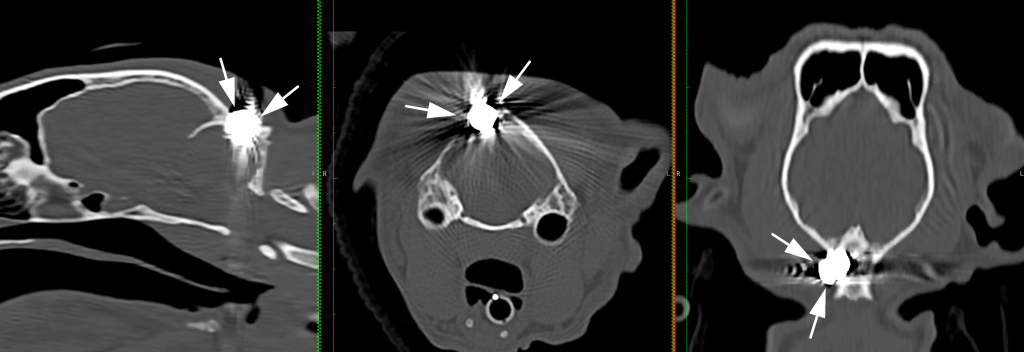

A young cat with a gunshot injury in the back of his head and depression fracture of the parietal bone successfully underwent a craniectomy at Davies Veterinary Specialists (Davies) in Hertfordshire to remove the pellet and repair the damage.